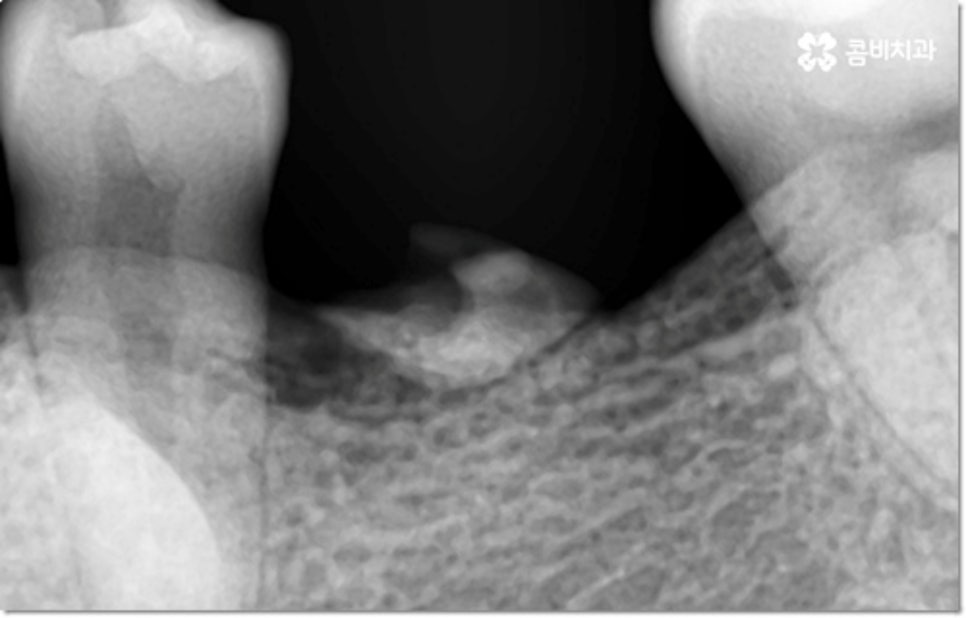

게다가 이러한 습관을 가지고 있으면 다른 정상 치아 역시 뿌리가 흡수되면서 짧아지는 치근 흡수가 일어날 수도 있습니다. 보통 치근 흡수는 교정 치료를 받을 때 간혹 너무 무리한 힘을 받은 치아에 부작용으로 나타나는 경우가 대부분이지만 교정과 상관없이 유전적인 질환 (갑상선기능항진증이나 파제트병 등)으로 인한 경우도 있고, 심각한 충격을 받은 치아 또는 매복치의 영향을 받은 인접 치아에 나타나는 경우도 있으며 말씀드린 것과 같은 구강악습관으로 인해 발생할 수도 있어요.

물론 갑자기 치아가 쑥 빠지거나 하는 것이 아니라 사진에서 볼 수 있듯이 치아 뿌리 끝부분이 둥글어지면서 짧아지는 정도이긴 하지만 아무래도 흔들림, 이시림 등의 불편함을 초래하고 치아와 잇몸을 약해지게 만들며 구강 건강 전체에 좋지 않은 영향을 줄 수 있으니 장기적으로 봤을 때도 이러한 습관은 바꾸시는 게 좋을 거예요.